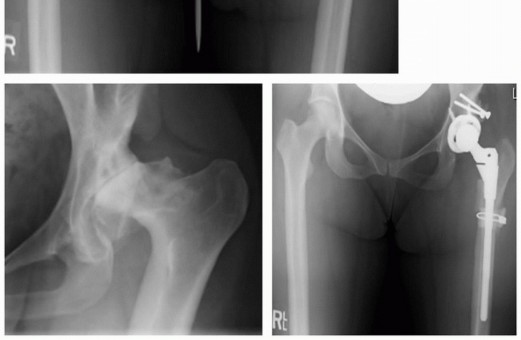

عندما تفشل العلاجات التحفظية وغير الجراحية في تخفيف الأعراض أو تصحيح التشوه، يصبح استبدال مفصل الورك الكلي (Total Hip Replacement - THR) خيارًا ضروريًا للكثير من المرضى البالغين المصابين بـ DDH المتقدم. ومع ذلك، فإن إجراء جراحة استبدال مفصل الورك لمرضى DDH يمثل تحديًا خاصًا ومعقدًا للغاية نظرًا للتشوهات التشريحية الفريدة التي تميز هذه الحالة. غالبًا ما يكون التجويف الحقي ضحلًا وصغيرًا، وموضعه غير طبيعي (أعلى وأكثر خلفية)، وقد يكون رأس عظم الفخذ صغيرًا أو مشوهًا، بالإضافة إلى قصر في عظم الفخذ وتشوهات في عظم الحوض. تتطلب هذه التحديات خبرة جراحية فائقة وتقنيات متقدمة لإعادة بناء المفصل بشكل فعال ودائم.

على الرغم من أن THR هو الحل الذهبي لمرضى التهاب مفاصل الورك المتقدم، إلا أن إجراؤه لمرضى DDH يمثل تحديات فريدة ومعقدة للغاية تتطلب خبرة جراحية متخصصة. هذه التحديات تشمل:

- التجويف الحقي الضحل وغير المتطور: التجويف الحقي يكون غالبًا ضحلًا جدًا أو صغيرًا، أو موجودًا في موضع مرتفع وغير طبيعي. هذا يجعل من الصعب تثبيت الكوب الاصطناعي بشكل آمن في الموضع الصحيح.

- نقص العظم في الحُق: قد لا يكون هناك ما يكفي من مخزون العظام لدعم الكوب الاصطناعي، مما يتطلب تقنيات ترقيع العظام.

- تشوه رأس عظم الفخذ: قد يكون رأس الفخذ صغيرًا أو غير منتظم، وقد يكون عنق الفخذ قصيرًا أو مشوهًا، مما يؤثر على اختيار مكونات المفصل الصناعي.

- قصر عظم الفخذ: غالبًا ما يعاني المرضى من قصر وظيفي في الساق المصابة، ويتطلب تصحيح هذا القصر أثناء الجراحة تخطيطًا دقيقًا لتجنب إصابة الأعصاب.

- مركز دوران الورك المرتفع: في حالات الخلع الشديد، يكون مركز دوران الورك أعلى من الطبيعي، مما يغير الميكانيكا الحيوية ويجب تصحيحه لضمان وظيفة جيدة.

يتطلب التغلب على هذه التحديات تخطيطًا دقيقًا قبل الجراحة باستخدام الأشعة المقطعية ثلاثية الأبعاد، واستخدام تقنيات جراحية متخصصة مثل ترقيع العظام لإنشاء تجويف حقي مناسب، وتقنيات إطالة الأنسجة الرخوة. وهنا يبرز دور الأستاذ الدكتور محمد هطيف، الذي يمتلك الخبرة والمعرفة اللازمة للتعامل مع هذه الحالات المعقدة بنجاح، مستفيدًا من التقنيات الحديثة لضمان أفضل النتائج.